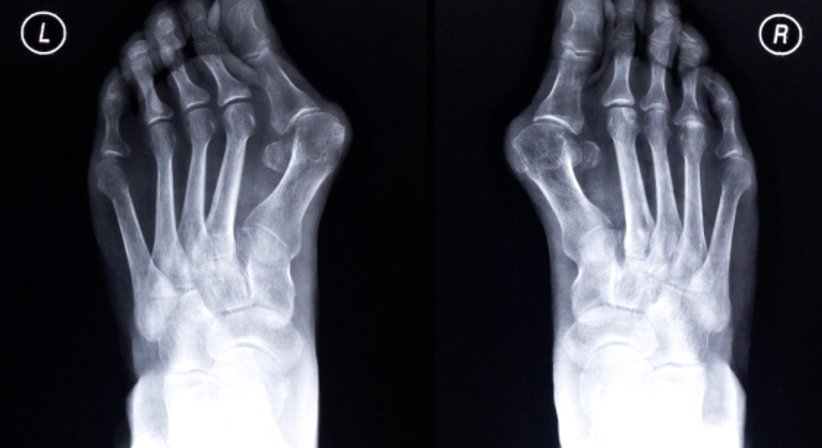

Hallux valgus

Der Hallux valgus wird umgangssprachlich als Frostbeule, aber auch als Ballenzeh oder Überbein bezeichnet. Die Deformation des Großzehenballens bzw. Fehlstellung der Großzehe ist oft auch mit einer anormalen Spreizung im Mittelfuß verbunden. Häufig geht dem Hallux valgus ein Spreizfuß voraus.

Der Hallux valgus kann unterschiedliche Ursachen haben. Der erbliche Faktor steht im Vordergrund, jedoch auch entzündliche Gelenksveränderungen oder das Tragen von zu hohen oder zu engen Schuhen kann zu Entstehung des Ballenzehs beitragen.

Die Fehlstellung macht sich in den meisten Fällen durch Schmerzen beim Gehen, v.a. bei der Abrollbewegung des Fußes, bemerkbar. Die Haut ist an der betroffenen Stelle einer dauerhaften Reizung ausgesetzt. Das kann zusätzlich zu Schwellungen und Entzündungen führen. Da der Verlauf fortschreitend ist, wird meist eine operative Behandlung empfohlen.